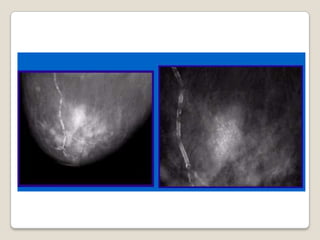

 Hallazgo frecuente, la mayoría se

asocian a patología benigna

 El análisis de su aspecto permite

clasificarlas como :

◦ BENIGNAS: NO requieren ninguna atención

◦ MALIGNAS: requieren biopsia para confirmar

◦ INDETERMINADAS:

 lesiones de baja sospecha: CONTROL

PERIODICO

 lesiones de mediana sospecha : BIOPSIA

Calcificaciones

   Benignas               Malignas

   Redondas               Irregulares

   Dispersas              Agrupadas

   Bilaterales            Unilaterales

   Grandes                Muy pequeñas

microcalcificaciones